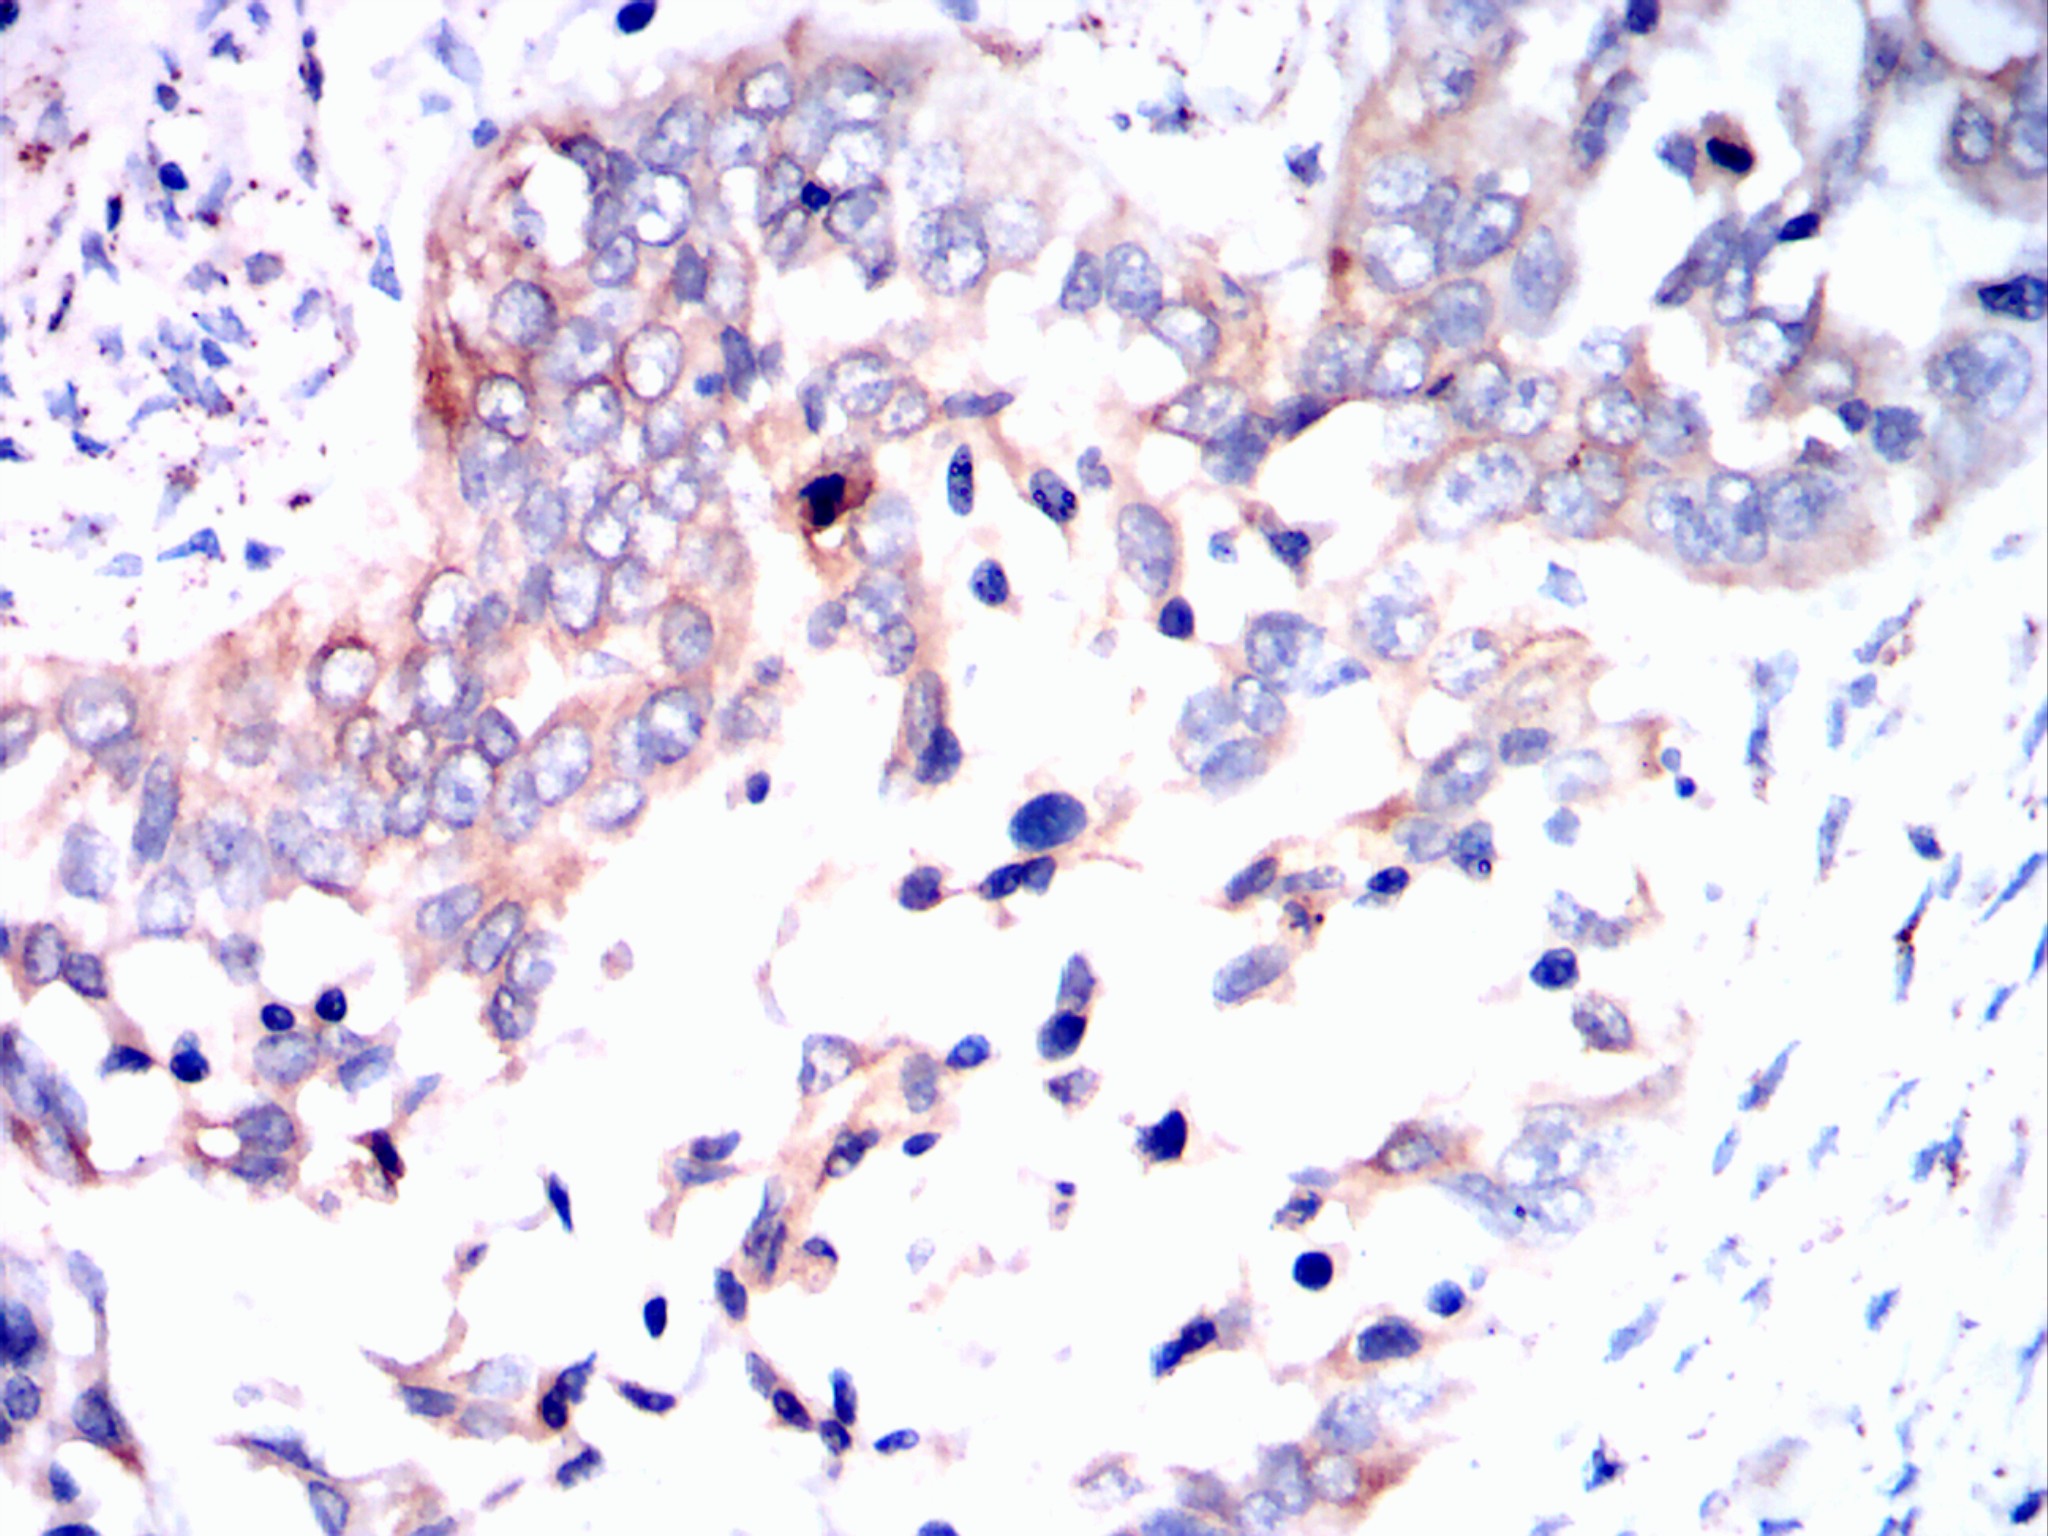

Immunohistochemical analysis of paraffin-embedded esophageal cancer tissues using ERBB3 mouse mAb with DAB staining.

Immunohistochemical analysis of paraffin-embedded esophagus tissues using *** mouse mAb with DAB staining.